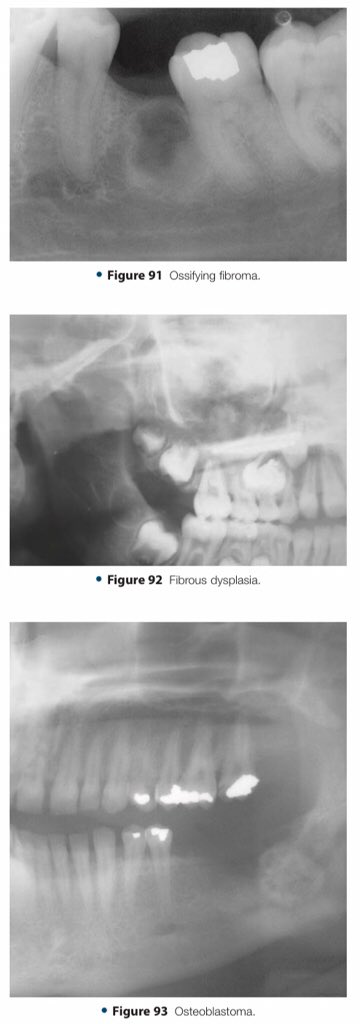

🔍| Differential Diagnosis Approach to Jaw Lesions. #aboutDent